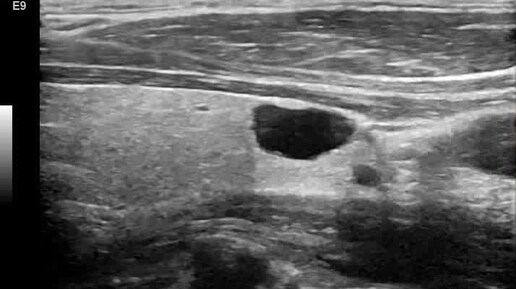

Видео к статье "Стратификация узлов щитовидной железы. TI-RADS-3" https://dzen.ru/a/Zv4svErHVi-eImKZ

Ультразвуковые находки от врача УЗД Зорина Я.П.